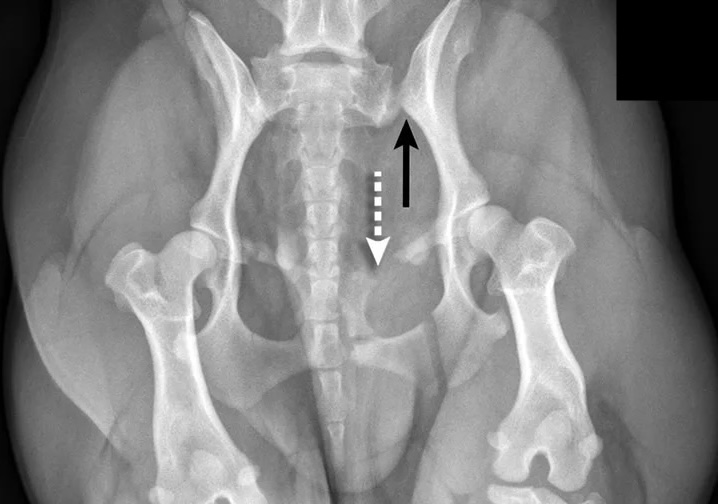

Перелом бедра у собаки

Перелом бедра у собаки 113 фотографий